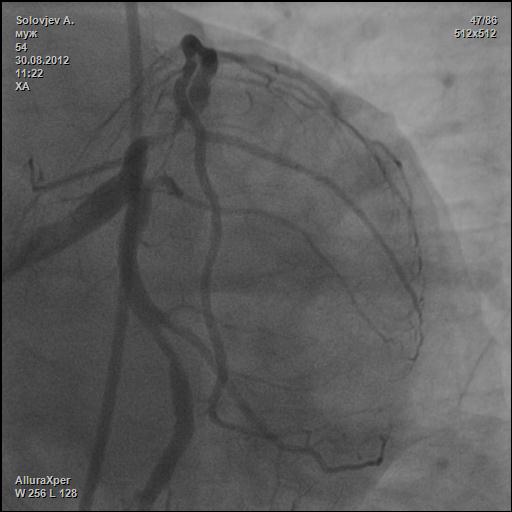

В проекции «Spider» - ЛКА и окклюзия ПНА смотрится понятнее (для меня естессно).

А белая стрелка показывает окклюзию диагональной ветки?

я хочу разобраться.

Больному было выполнено 2 АКШ и 1 МКШ.